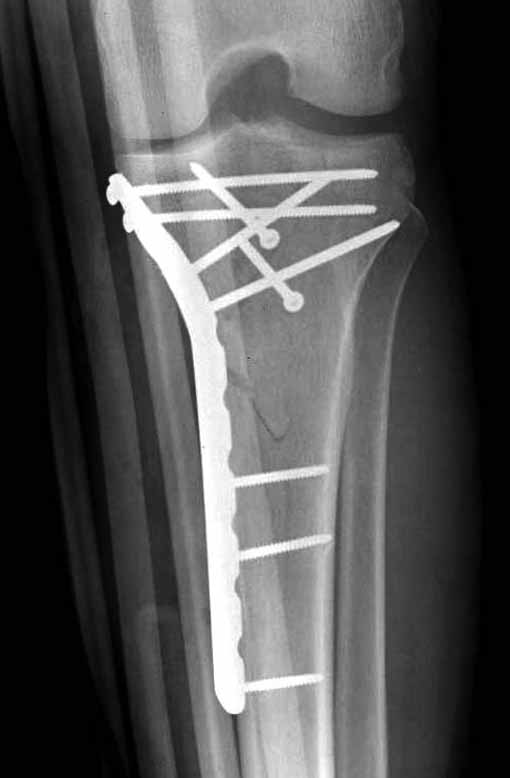

В приложении этапы фиксации пластиной Synthes для плеча при переломе медиального мыщелка.

Имя     : 2 medial column tibial plateau.JPG

Тип     : image/jpg